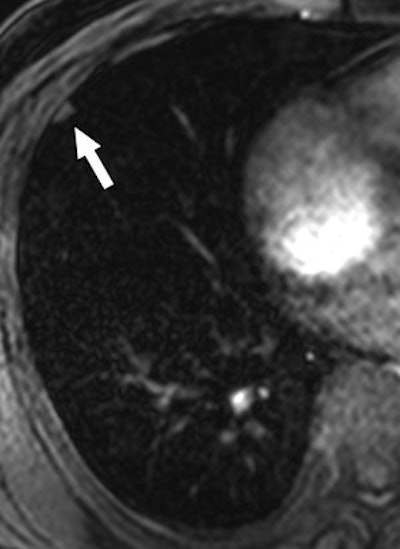

| Same patient as above. T1-weighted 3D turbo field-echo (B) and T2-weighted triple inversion black blood turbo spin-echo (C) images show 9-mm nodule (arrow) in right middle lobe. Nodule is subtle in C and not easily visualized. |